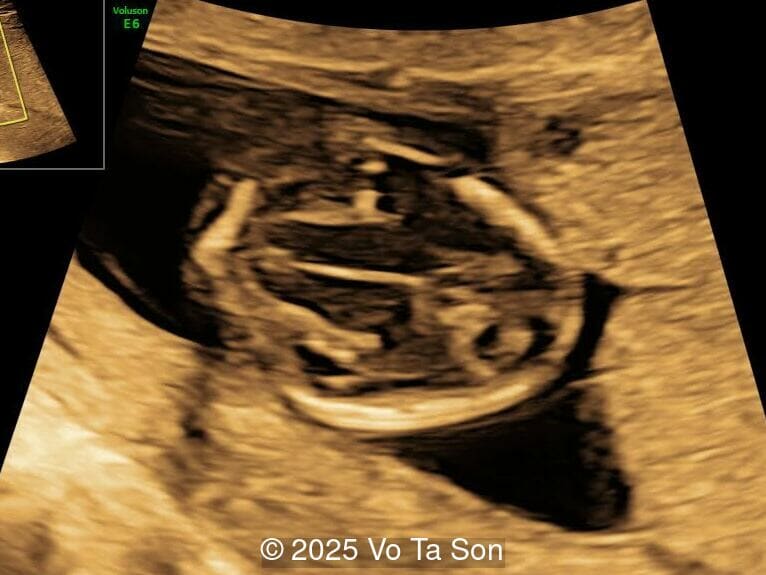

A woman underwent routine prenatal screening at 13 weeks. The non-invasive prenatal test (NIPT) showed low risk for common aneuploidies including trisomy 21, 18, and 13. However, first-trimester anomaly scan revealed multiple fetal anomalies.

Please describe the abnormalities and provide a syndromic diagnosis that best fits the presentation.